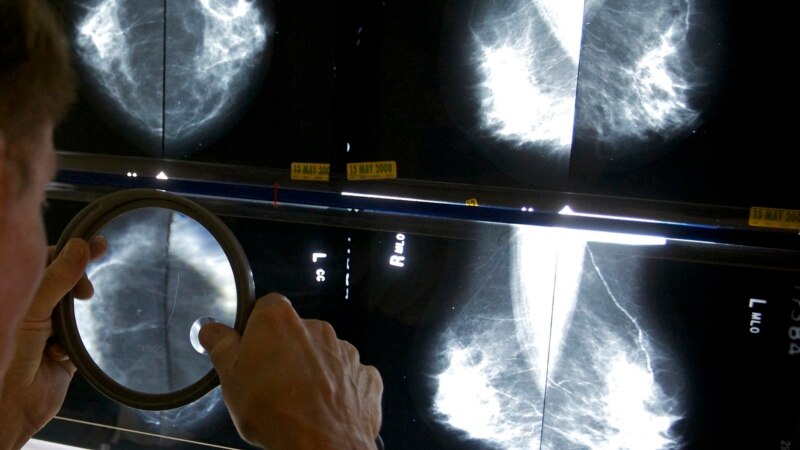

Study: Vitamin Supplements May Harm Breast Cancer Treatment